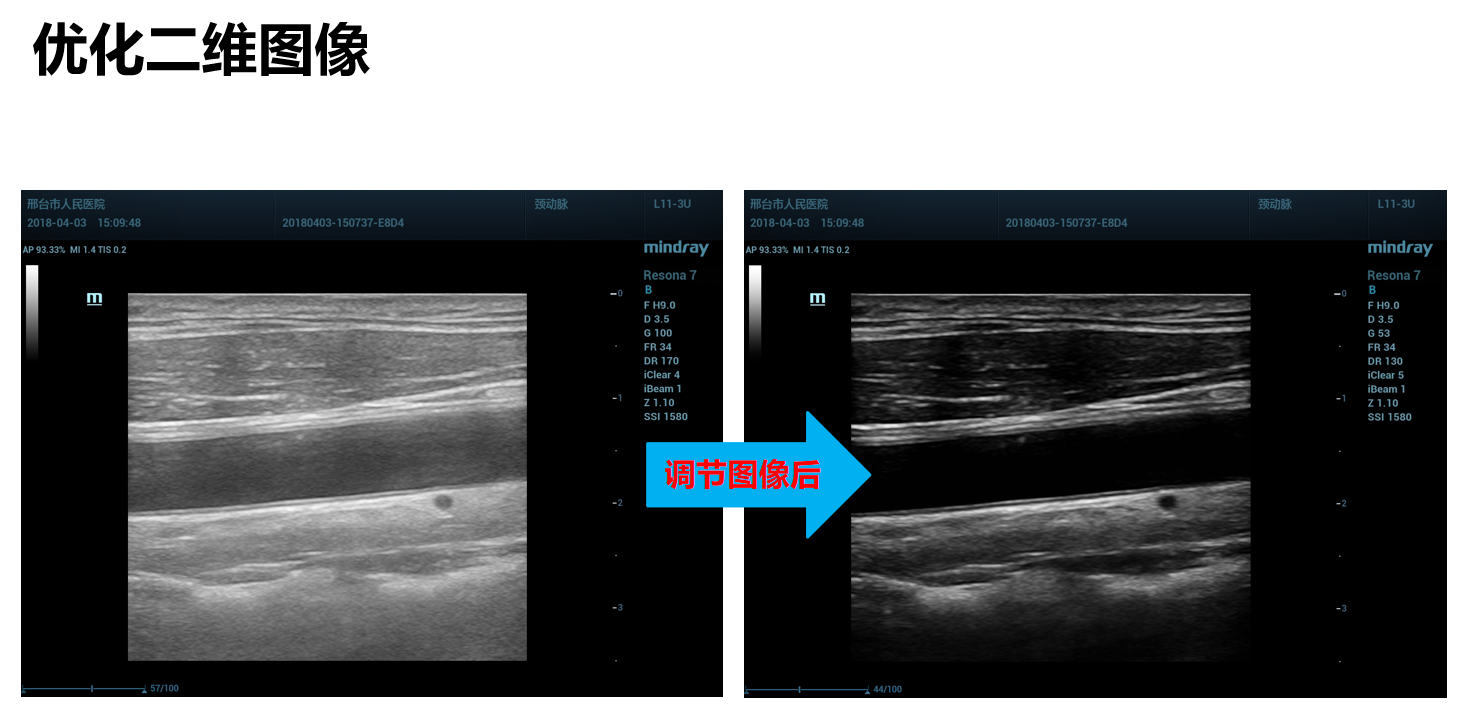

Gain是图像的总增益,是控制整场图像回声的亮度,增加增益使图像亮度增加,可以观察到更多回声信号,但同时也会带来更多噪声。

这幅图像就是增益过高,图像亮度太亮,得到回声信号很多,但同时也有很多噪声。经过降低增益就会得到这幅质量很好的图像。

动态范围是机器对强弱信号接收和处理的范围,他显示图像的灰阶级别数,动态范围增加信息量增多,可以显示微弱的信号,使图像变得柔和,但是动态范围太大,图像发雾。动态范围减低,信息量减少,导致图像的对比度高,微弱的信号被除去,灰阶层次减少,图像相对清亮。总之,动态范围实际表现,就是图像的对比度。

提高对比度的方法有:降低增益;降低动态范围;打开谐波;选择适当的灰阶图谱/效果图;调高空间复合成像iBeam和斑点噪声抑制iClear。

提高对比度的方法有:降低增益;降低动态范围;打开谐波;选择适当的灰阶图谱/效果图;调高空间复合成像iBeam和斑点噪声抑制iClear。